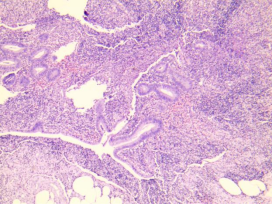

慢性阑尾炎

多由急性或亚急性阑尾炎发展而来,亦可一开始就是慢性炎,主要病变为阑尾各层不同程度纤维化和淋巴细胞、浆细胞浸润。

黏膜固有层大量浆细胞及淋巴细胞,

纤维组织增生